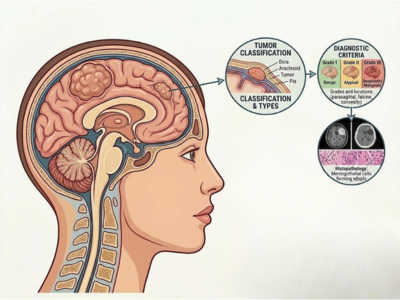

Types of Brain Tumors Treated by Dr. Sanjog Chandana

Every brain tumor is unique, and so is the treatment for it. Dr. Sanjog Chandana treats a variety of brain tumor types, tailoring his approach based on your specific condition. Some of the brain tumors Dr. Chandana treats include:

Gliomas

Tumors originating in the supportive glial cells of the brain.

Meningiomas

Tumors that form in the meninges, the protective layers around the brain.

Pituitary Tumors

Tumors that grow in the pituitary gland, which controls hormone production.

Metastatic Brain Tumors

These are brain tumors that spread from cancers elsewhere in the body.

Acoustic Neuromas

Tumors that affect the hearing and balance nerves.

Brain Stem Tumors

Tumors in the brain stem, which controls essential body functions like breathing.

Each type of tumor requires a specialized treatment approach. Dr. Chandana’s expertise ensures that you receive the most appropriate care for your specific diagnosis.

Wondering about the different types of brain tumors? Let’s take a closer look at the conditions Dr. Sanjog Chandana specializes in treating to ensure you get the right care.